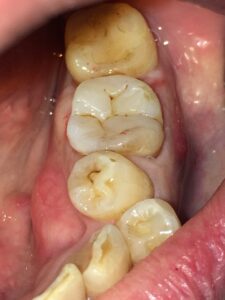

欠損が大きいので、一般的にはクラウンで被せて治療することになりますが、できるだけ歯を削らず回数少なく白い材料で治したいという希望があり、ダイレクトボンディングによる修復を行うことにしました。

術後写真。臨在歯に色調を合わせ咬合面にもステインを付け自然な感じに修復しました。

(ステインについては真っ白に修復したいという方も多いので、患者さんと相談して付けるかどうか決めています)

治療回数:1回(約60分)